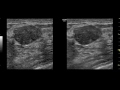

Если у вашей кошки обнаружена опухоль на животе, важно незамедлительно обратиться к ветеринарному врачу, чтобы получить профессиональную консультацию и диагностику. Ветеринар проведет осмотр кошки, возможно возьмет образцы для биопсии и назначит дополнительные исследования, такие как ультразвуковое исследование или рентген.

У опухолей на животе кошки могут быть разные причины, включая доброкачественные и злокачественные опухоли. Дальнейшее лечение будет зависеть от результатов диагностики и определения типа опухоли. Ветеринар может рекомендовать хирургическое удаление опухоли, химиотерапию, радиотерапию или другие методы лечения в зависимости от конкретной ситуации.

Шишка на животе у кошки под кожей, опухоль